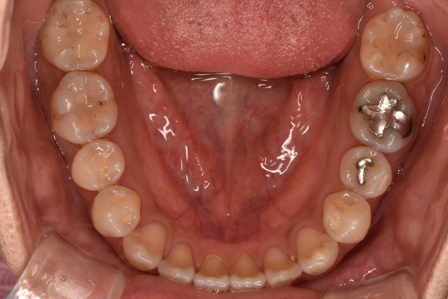

治療前

| カウンセリング・診断結果 | 診察したところ、上の前歯の真ん中に隙間が空いている状態でした(正中離開)。 |